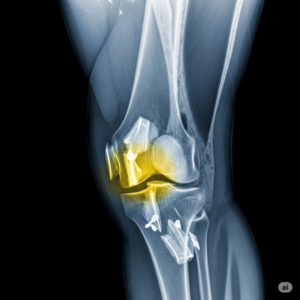

A artroscopia do joelho é um procedimento minimamente invasivo indicado para diagnosticar e tratar problemas internos dessa articulação, como lesões de menisco, ruptura de ligamentos e danos na cartilagem, sendo considerada uma forma moderna e precisa de cirurgia de joelho. Durante a cirurgia, o médico utiliza uma microcâmera e instrumentos específicos para reparar ou remover tecidos lesionados com precisão. Esse método permite avaliar a articulação em detalhes e tomar decisões cirúrgicas mais seguras.

A artroscopia do joelho é indicada para tratar diversas condições, incluindo rupturas de menisco, lesões de ligamentos, fragmentos ósseos soltos, inflamações da membrana sinovial e lesões de cartilagem. O procedimento também é eficaz para corrigir casos de instabilidade articular, promovendo maior estabilidade e função ao joelho. Graças à sua abordagem minimamente invasiva, permite intervenções precisas com menor dor e tempo de recuperação reduzido.

A decisão de realizar a artroscopia deve ser baseada em exame clínico detalhado e exames de imagem, como ressonância magnética, para identificar corretamente a lesão. Em muitos casos, a cirurgia é indicada quando tratamentos conservadores, como fisioterapia e uso de medicamentos, não trazem melhora satisfatória. Dessa forma, o procedimento oferece alívio da dor, melhora da mobilidade e preservação da estrutura saudável da articulação.